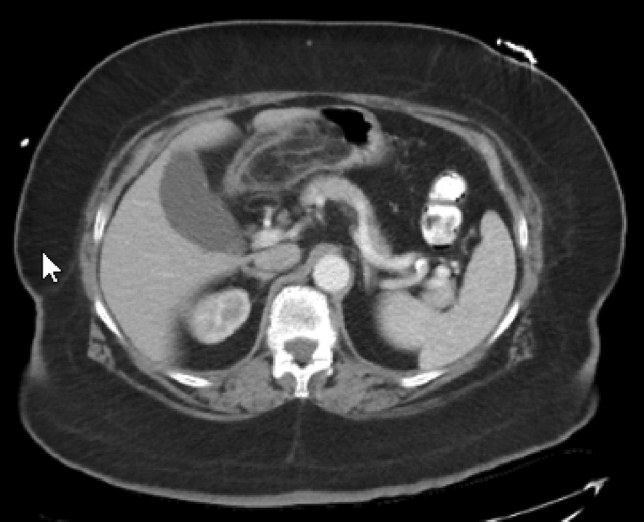

M. Carolina Jimenez, MD; Robert F. Cubas, MD; Jose M. Martinez, MD; University of Miami/Jackson Health System

Introduction: Biologic mesh has been used in clean-contaminated and contaminated fields and while wound infection rates may be high, infection is usually superficial and graft removal is unusual. Biologic mesh has been reported to have higher recurrence rates and poor incorporation into native tissue in comparison to synthetic mesh. Currently, there is no consensus on mesh preservation treatment in cases of mesh infection after hernia repair.

Methods: We present a 72-year-old male with prior radical cystectomy and neobladder creation complicated at the time by neobladder-cutaneous fistula and wound infection requiring revisional surgery and incisional hernia repair with mesh. He developed a large recurrent incisional hernia and underwent open hernia repair with bilateral anterior component separation, extensive lysis of adhesions, removal of prior mesh, and placement of a biologic mesh (Strattice™ RTM) in an underlay and onlay fashion. Intraoperatively, the defect measured 20 cm long by 14 cm wide. Postoperatively, he was treated for neobladder infection and CT cystogram found no extravasation from the neobladder. He presented to the emergency department 6 weeks after surgery with spontaneous partial midline wound dehiscence, with exposure of the onlay mesh and drainage of clear fluid, which was confirmed to be urine by fluid creatinine level. Repeat CT scan demonstrated a filling defect at the anterior wall of the neobladder with contrast leaking into a contained collection interposed between the anterior abdominal wall and the underlay mesh, extending superiorly between the small bowel loops and dehiscence of the midline abdominal wound. The patient was treated with a course of antibiotics and indwelling Foley catheter and bilateral nephrostomy tubes for urine diversion.

Results: Three months later, repeat CT cystogram demonstrated resolution of the leak and the nephrostomy tubes and Foley catheter were removed. The patient has continued daily wound care with significant reduction in size of the midline wound and increasing granulation tissue around the onlay mesh. He has not required further admissions to hospital and there has been no hernia recurrence so far.

Conclusion: In the appropriate setting, contaminated biologic mesh after surgery may be treated with medical management with adequate wound closure, avoiding the need for surgery and mesh explantation.